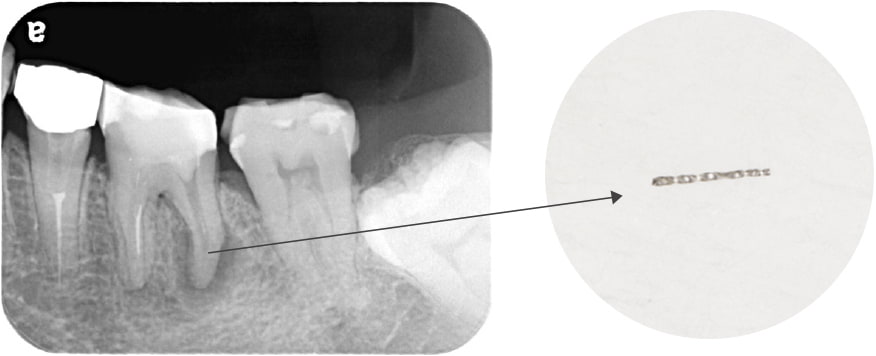

折れて残っていた機具を除去

根管の中を洗浄し、無菌に近い空の状態にした。

根管の中を封鎖し終了。

治療後病気がなくなり骨が再生した